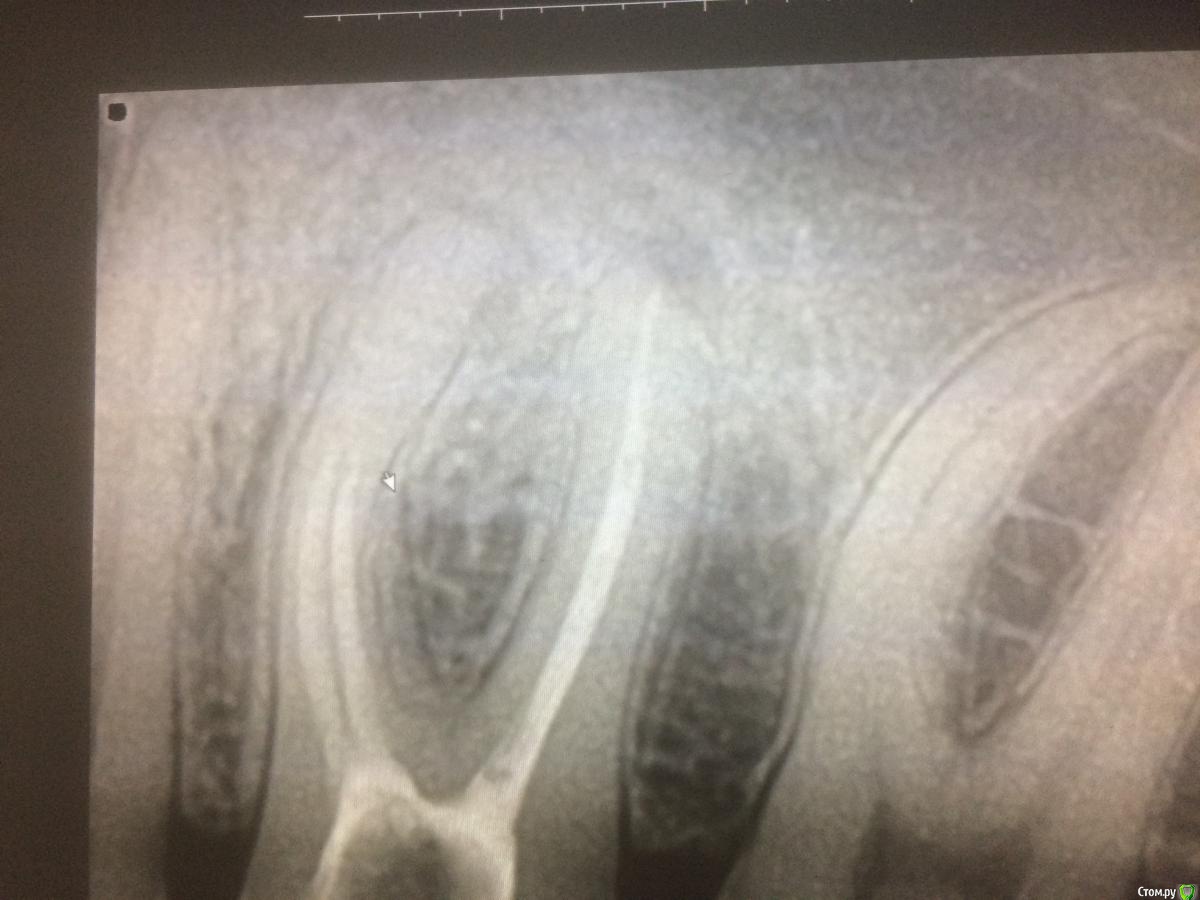

xMeDx Опубликовано 31 июля, 2019 Поделиться Опубликовано 31 июля, 2019 Начальная ситуация :пациент жалуется на застревание пиши между 4.5,4.6.Делаю снимок 4.6-большая пломба и слегка прикрыты устья дистального канала материалом а так канал пустой .Медиальные запломбированы на половину .Пломбировка рыхлая .На апексах легкое разряжение костной ткани.Легкая боль при перкуссии. Распломбировал,обработал химически.На неделю кальций и временная пломба.Через 5 дней пациент приходит с жалобами на ноющие боли которые особо и не беспокоят но спать не дают и обезболивающее 2 раза в день (это со слов пациента жалобы ).Открываю каналы.Обрабатываю .Закрываю постоянным тиэдент +гутта.Назначаю нпвс.Это вчера.Сегодня зуб болит так же.Причина просто реакция на кальций и нужно время или может быть что-то ещё ? Ссылка на комментарий

red_butler Опубликовано 31 июля, 2019 Поделиться Опубликовано 31 июля, 2019 А что должно смущать?Материал в медиальных каналах недоведенный ?работа без кофера, не проведена полноценная механическая и возможно медикаментозная обработка 1 Ссылка на комментарий

xMeDx Опубликовано 31 июля, 2019 Автор Поделиться Опубликовано 31 июля, 2019 работа без кофера, не проведена полноценная механическая и возможно медикаментозная обработка Может быть механическая и хромает но гипохлоритом все обрабатывалось как надо.К стати последнее фото не последнее.Там кальций.Так механическая обработка причина боли ?И как купировать ?Только перелечивать ? Ссылка на комментарий

vse32 Опубликовано 31 июля, 2019 Поделиться Опубликовано 31 июля, 2019 Смущает ещё близость нижнечелюстного канала До нч канала там еще как до Канадской границы. Близость канала может смущать хирурга при травматичном удалении или терапевта если он делает очень большой овертритмент.Канал во всех этих случаев болей не даст, а вот повреждение нерва в канале даст онемение. Временное или постоянное. Зависит от характера травмы.Про коффер, качество и прочее промолчу. У каждого свое, я так понимаю Вы врач начинающий. Научитесь еще. Главное форум почаще читайте и не бойтесь задавать глупые вопросы, а так же получать на них не всегда приятные ответы. Ну а по существу вопроса. Любая боль после эндодонтического вмешательства это результат проникновения чего либо за апекс.1. Механическая причина - оверинструментация даже на 1 мм может дать боль. Вспоминаем. Апекс это не рентгологическая верхушка корня, апекс чуть раньше. И выводя инструмент до рентгенологической верхушки Вы уже сделали оверинструментацию.2. Химико-биологическая причина. а) Проталкивание за апекс содержимого канала. б) Вывод любого материала (силлер, кальций, пульпосептин) - это все может вызвать реакцию периодонта. Эти вещества там лишние. в) Проникновение ирриганта. - смотри пункт б)Все это вызывает обострение процесса, но если канал был качественно обработан механически, медикаментозно и впоследствии хорошо обтурирован - все пройдет. 6 Ссылка на комментарий

red_butler Опубликовано 31 июля, 2019 Поделиться Опубликовано 31 июля, 2019 Так механическая обработка причина боли ? в каналах остался бактериальный субстрат плюс Химико-биологическая причина Ссылка на комментарий